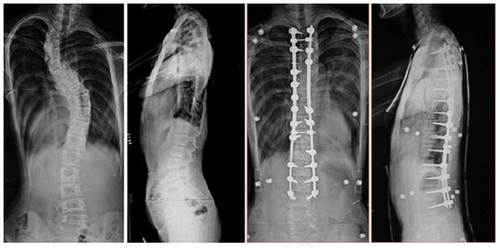

细心观察生活的人会发现周围有很多站姿不是很直的人。这在学名上来讲叫做脊柱畸形。脊柱畸形有一些是由于先天的因素形成的,但是有一些却不是。那么,脊柱畸形是由于什么原因导致的呢?

1、先天成因。有许多儿童在幼儿时期,由于一些先天性的因素造成了脊柱的畸形。这样的畸形是很难治愈的。有一些幼儿因为错过了最佳治疗时期,从而造成了无法挽回的后果。

2、后天成因。后天的脊柱畸形,主要是因为先天的疾病引发的并发症或者是坐姿不正确等导致的。其各种各样的因素都有可能,具体原因还需要去医院做具体的检查才能知晓。

3、疾病成因。后天疾病的成因主要是因为神经纤维瘤导致的。患有神经纤维瘤的患者,大部分都会有脊柱畸形的毛病。所以在患有神经纤维瘤的先期就要做出患有脊柱畸形的准备,做好预防。

脊柱是用来支撑人体的组成部分之一。当脊柱发生病变,甚至是畸形时一定要及时去医院就医。以最大限度的确保有矫正回来的可能性。